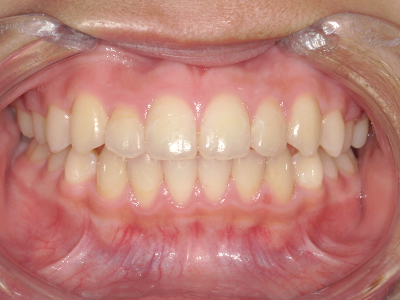

ないき歯科クリニックでは、これからあごが成長していくお子様や、歯並びが気になる成人の方など、さまざまな年代の方に対して矯正治療を行っています。

歯並びやかみ合わせを正しく整えると、笑顔や発音の自信につながり、むし歯・歯周病・口臭の予防にも役立ちます。

矯正装置を装着し、調整しながら少しずつ歯を移動させ、歯並びを整えていきます。